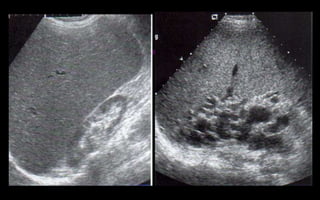

Nefrolitiasis renal

 Frecuentes

 12% de la población

 >Varones

 UUP, Cruce de los

iliacos y UUV

 UUV (75-80%)

HIDRONEFROSIS

Nefropatía crónica

 Aumento de la

ecogenicidad renal

 Disminución del

tamaño

 Pérdida de la

diferenciación seno-

parénquima